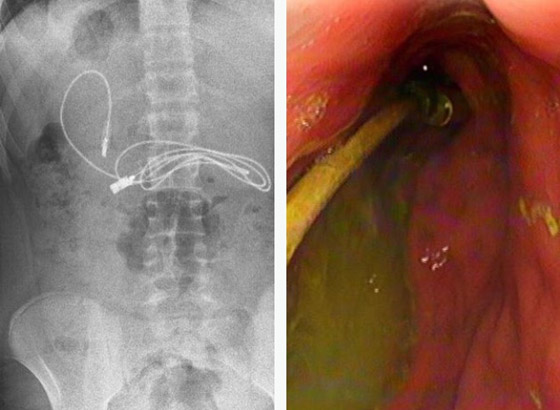

صدم مراهق الأطباء، بعد نقله إلى أحد مستشفيات تركيا وهو يعاني من غثيان شديد وآلام مبرحة في معدته، إذ أظهرت الأشعة المقطعية، ابتلاعه سلك شاحن طوله 90 صنتيمتراً. وخضع المراهق الذي لم تكشف هويته، إلى عملية عاجلة لاستخراج السلك من معدته، ليتبين أنه ابتلع ربطة شعر، أيضاً.

وقال الطبيب الذي أشرف على الجراحة، إن العملية كانت معقدة لأن أحد طرفي السلك مَر إلى الأمعاء الدقيقة. ولحسن الحظ، تعافى المراهق، 15 عاماً، سريعاً بعد العملية وعاد إلى منزله في ديار بكر بصحة جيدة.